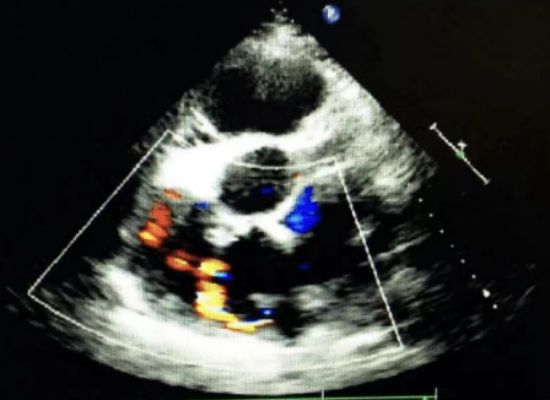

一、冠状动脉—右房瘘(图5)(图6)

超声切面:主动脉半轴切面(非标切面)

超声可见:瘘管开口于右心房,包括引流入腔静脉,冠状静脉瘘,左位上腔静脉。引流入右心房的部位常为右心房的前壁,房间隔的右房面及上腔静脉

图5 左冠状动脉—右房瘘

图6 彩色多普勒可见血流入右心房